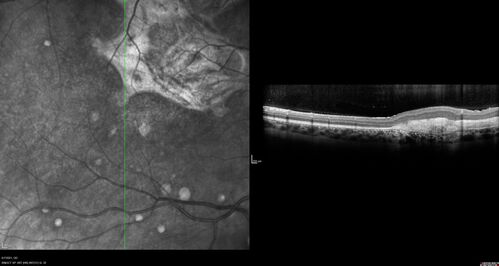

PIC which evolved into Subretinal Fibrosis

27 year old female VA 20/200 right eye 20/20 left eye. Right was treated with lucentis. When extended to 3 months, the fibrosis got much worse